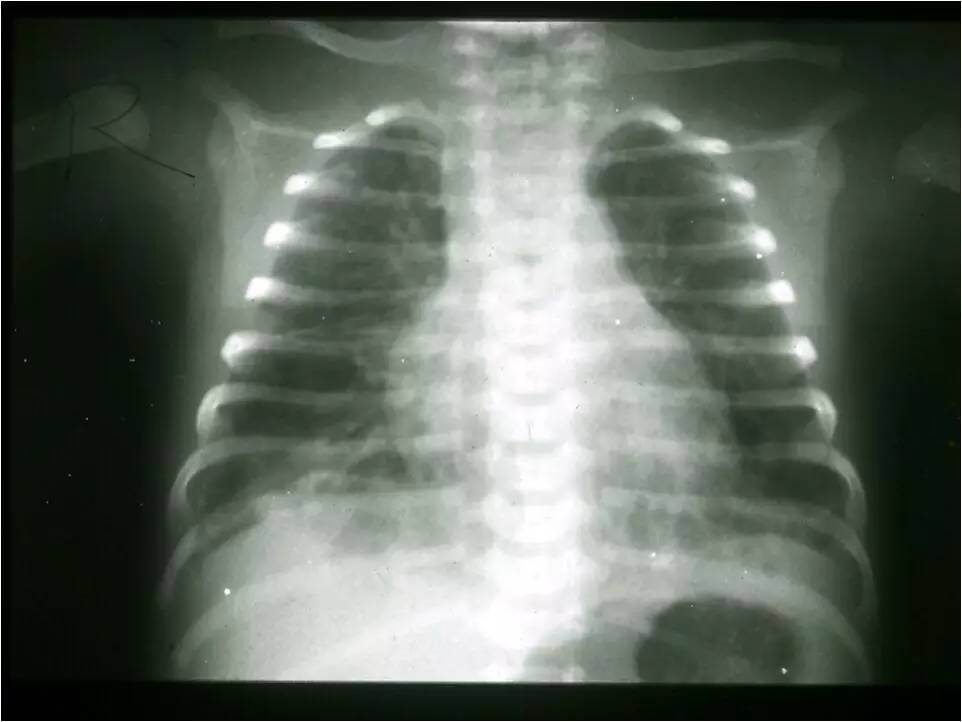

MAS影像学表现

临床特征